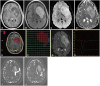

The imaging and clinical management of patients with brain tumor continue to evolve over time and now heavily rely on physiologic imaging in addition to high-resolution structural imaging. Imaging remains a powerful noninvasive tool to positively impact the management of patients with brain tumor. This article provides an overview of the current state-of-the art clinical brain tumor imaging. In this review, we discuss general magnetic resonance (MR) imaging methods and their application to the diagnosis of, treatment planning and navigation, and disease monitoring in patients with brain tumor. We review the strengths, limitations, and pitfalls of structural imaging, diffusion-weighted imaging techniques, MR spectroscopy, perfusion imaging, positron emission tomography/MR, and functional imaging. Overall this review provides a basis for understudying the role of modern imaging in the care of brain tumor patients.